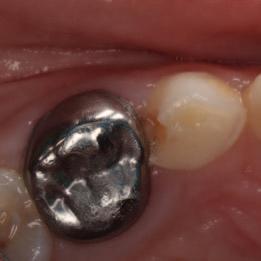

Create a flipbook

Issuu converts static files into: digital portfolios, online yearbooks, online catalogs, digital photo albums and more. Sign up and create your flipbook.